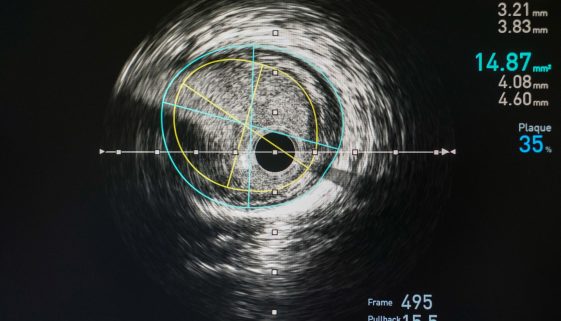

تُعد القسطرة العلاجية للشرايين الطرفية من الإجراءات الطبية المهمة التي تُستخدم لعلاج انسداد أو ضيق الشرايين في الأطراف، مثل الساقين والذراعين. يمكن أن تؤدي هذه الحالات إلى مشاكل صحية متعددة، بما في ذلك الألم والتعب والإصابة بالقرح. في هذه المقالة، سنقدم لك نصائح وتعليمات تثقيفية مهمة لتوضيح هذا الإجراء للمرضى […]